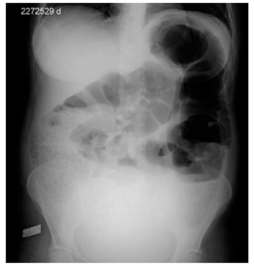

Mulher de 69 anos foi atendida com queixa de dor abdominal em cólica havia 3 dias, acompanhada de distensão, náuseas, hiporexia e parada de eliminação de flatos e fezes. Relatou que, havia cinco meses, apresentava emagrecimento e episódios de dores abdominais, associados a obstipação intestinal. Tem antecedente de hipertensão arterial sistêmica e está em uso de losartana 50 mg/dia. No exame físico, apresentava-se consciente, contactuante, descorada ++/4, desidratada +/4, abdome distendido, globoso, hipertimpânico em andar superior, levemente doloroso, com massa palpável em hipogástrio, descompressão brusca negativa. Realizou exames laboratoriais e radiografia de abdome, cuja imagem é apresentada a seguir.

Considerando as informações desse caso e a imagem anterior, assinale a opção que indica corretamente o diagnóstico e o achado de imagem, respectivamente.